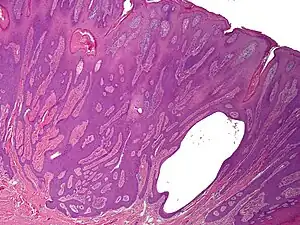

Syringofibroadenoma is a cutaneous condition characterized by a hyperkeratotic nodule or plaque involving the extremities.[1]:668

It is considered of eccrine origin.[2]